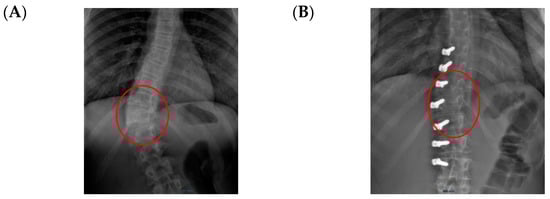

Figure 1.

(A) Thoracic scoliosis treated with Gruca Springs. (B) Double curve scoliosis treated with Gruca Springs.

From Mineiro’s archives (Figure 1), we can see that the posterior tether did work on the coronal plane for thoracic, thoracolumbar, and even double curvature scoliosis, but at that stage, orthopaedic surgeons were not concerned about the sagittal profile. Therefore, there are no lateral radiographs from these patients. In summary, looking back into the past, we can say that the posterior tether works for correcting the coronal scoliotic deformity in the adolescent growing spine (thoracic and thoracolumbar), but what would happen to the hypokyphosis of the spine in the lateral plane?